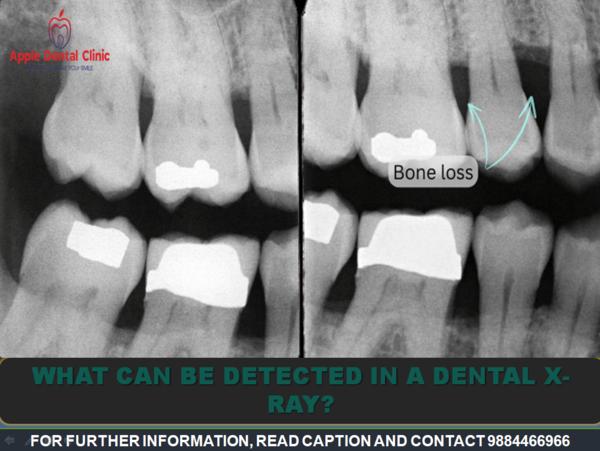

BEST ORAL CARE IN MMDA! Clearly, X-rays give the dentist a lot of valuable information. If you’re a...

BEST ORAL CARE IN ANNA NAGAR! We use dental X-rays to detect or rule out a variety of oral health i...

BEST ORAL CARE IN AMINJIKARAI! Among the most helpful advances in oral health has been the use of X...